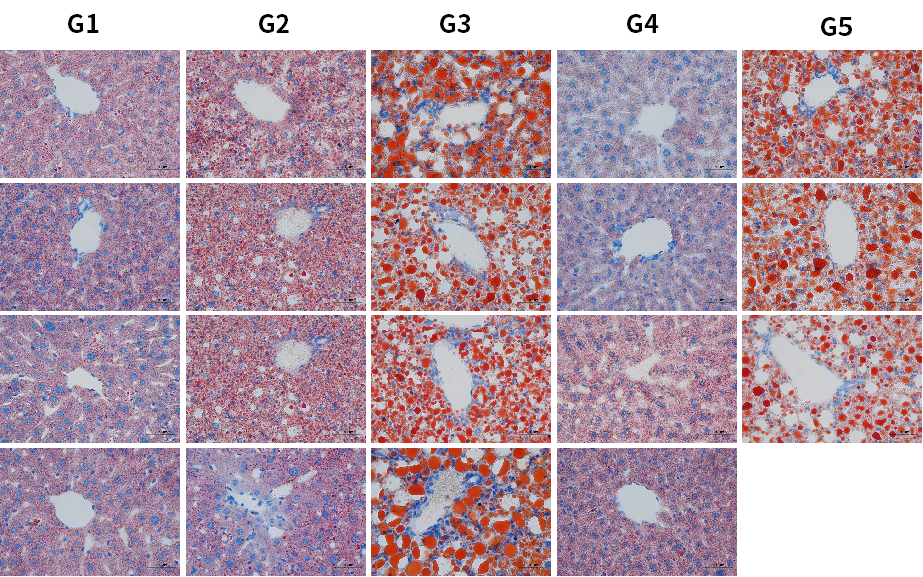

图9. HSD诱导6周后各组小鼠油红O染色代表图。结果显示,HSD饮食诱导下,肝脏特异性过表达hPNPLA3 I148M小鼠出现明显脂滴(G3,G5)。